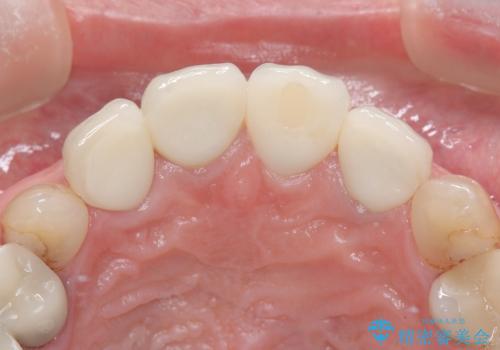

- 治療計画

- 患者様は前歯の審美的な改善を希望されて来院されました。診査の結果、左上1の歯は過去の根管治療により歯根が破折していることが判明し、保存が難しい状態でした。そのため、**長期的な予後を考慮し、抜歯と同時にインプラントを埋入する「抜歯即時インプラント」**を計画。また、隣接する左上2の歯には感染が見られたため、歯根端切除術を同時に行い、感染の除去と治癒を促しました。右上1・2については、セラミッククラウンによる審美修復を行う方針としました。

左上1は抜歯と同時にインプラントを埋入し、骨や歯ぐきの形態を維持しながら治療を進めました。左上2は歯根端切除術により感染部位を除去し、保存治療を実施。右上1・2も含めた前歯4本をセラミッククラウンで修復し、自然な色調と形態を再現しました。治療後は、噛み合わせの安定とともに、美しく自然な前歯を回復することができました。患者様からも「見た目がとても自然で、自信を持って笑えるようになった」と喜びの声をいただきました。